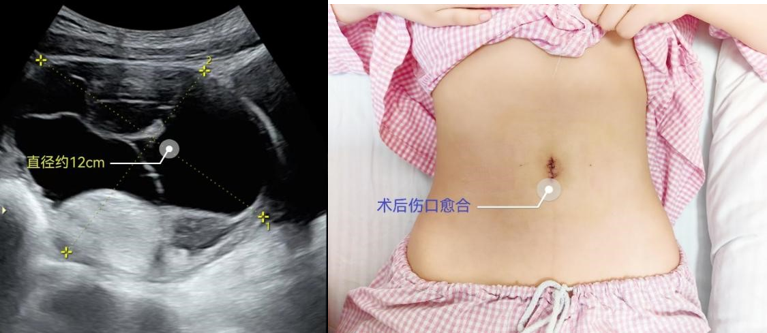

近日,13岁的小姑娘小张近来月经有些不规律,在妈妈的陪同下来到独墅湖医院妇产科侯文杰副主任门诊就医。本以为只是月经问题,超声检查却发现了小张盆腔有着12公分的巨大畸胎瘤,一时间吓坏了母女俩。虽既往未发生畸胎瘤相关急腹症,平时也没有任何不适,但若不及时手术对小张终是一个巨大的隐患,加之学业繁重时间耽误不得。妇产科团队遂启动了快速入院机制,安排小张住院并制定了治疗方案。

侯文杰副主任团队为小张实施了经脐单孔腹腔镜手术。由于囊肿巨大,小姑娘骨盆尚未达到成年人水平,狭小的操作空间给术者带了重重阻力,巨大的畸胎瘤囊壁极度菲薄,但为了最大限度保护卵巢皮质,手术全程没有使用能量器械止血。凭借着娴熟的技术以及成员之间的默契配合,侯文杰副主任团队用时20分钟就完整切除了肿瘤,最大限度保留了卵巢组织,并且通过缝合塑性恢复了卵巢的正常结构,最大程度保障了患者的生育能力。术后第三天,小张顺利出院,一周后就回到课堂继续学业了。